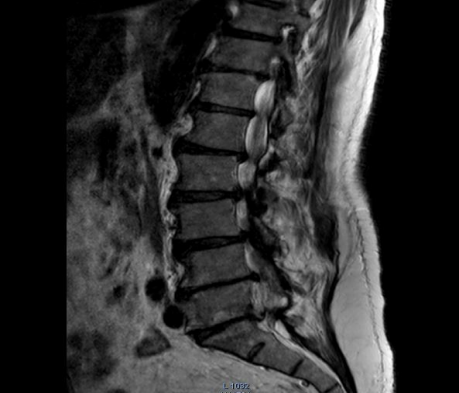

After two years of these events, when he complained of back pain with sciatica spreading to the right lower limb, we performed an MRI of the back and consulted with our neurosurgeon colleagues at Nene Teresa hospital No 5, my dear friend. Dr. Artid Lameh underwent laminectomy. Dr. Artid's opinion was that it is better for screw patients to undergo surgery with screws so that the body has more strength and consistency, especially in movements but the patient refused to accept such a limitation and only agreed to undergo a laminectomy. The patient's argument was that if he accepted the surgery with screws, his limitations would increase, which he did not want. It was interesting that despite the fact that the operation Lamicectomy surgery was performed on the 4th and 5th vertebra, the patient seemed very satisfied. Two years after the surgery, the patient complained of back pain again, and after doing a Lumbo-sacral column  MRI for a new evaluation, I asked my friend Dr. Artid Lameh to re-examine him. After examining the patient's MRI and clinical examinations, Dr. Artid Lame wrote to me that unfortunately, nothing more can be done for the patient anywhere. Considering his old age, the patient should accept the existing conditions and adapt himself... Earlier, my colleague, Dr. Daritan Tozeh, an orthopedic  surgeon  hospital, told me that nothing could be done for the patient. It is right for him to accept this situation. In February 2023, according to my old acquaintance with the patient, I called him to tell him the opinions of the doctors. When I was doing his clinical examination on the examination bed, my mind was occupied with two serious issues. Due to very severe atrophy of the thenar and hypothenar muscles of the hands, along with the atrophy of the bilateral muscles of the legs, which had progressed a lot compared to two years ago and the situation had worsened. For me, these muscle atrophies were very unexpected. At the same time, I could not recognize it. Until this month, I asked my very good friend, Mrs. Dr. Mimoza Spahio, a neurologist, who was helpful in diagnosing and treating many of my patients, to see her as well. Interesting and rare is Charcot- Marie- Tooth. The arguments she gave, I was also convinced that what she said was completely correct. Especially the fact that she said that I had faced similar cases in the past, but what is the cause of this disease.

Figure 1

Figure 2

Figure 3